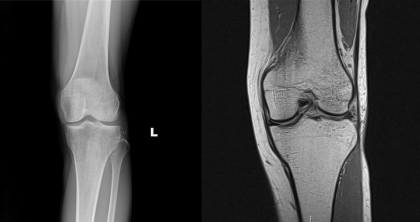

2019년 5월 5일 일요일 오랜만에 넷이 모여서 찜질방도 가고 외식도 하고 아울렛도 갔다. 다리가 너무 아파서 앉을 곳을 찾으려고 애쓰고 있어요. 어느 순간 절뚝거리고 있다는 걸 깨달았다. 그래도 이렇게 4명이서 모이는게 정말 힘들고, 신나게 놀아서 참았습니다(ㅎㅎ) 2019년 5월 8일 수요일 무릎이 반대 방향으로 휘어지려고 하는 것처럼. 2019년 5월 9일 목요일, 다리가 심하지 않아 성형외과를 보기로 했다. 개인병원보다 종합병원이 낫다는 생각에 창원에 있는 병원을 찾았다. 엑스레이는 아무 것도 보이지 않았고 의사는 나에게 영향을 받은 다리를 보라고 했습니다. 바지를 걷어 올렸을 때 다리에 멍이 든 것을 보고 무서웠습니다. 부상으로 인한 멍이 아니냐고 물었다.(웃음) 의사 선생님이 증상 설명을 듣고 쪼그려 앉은 자세로 무릎을 모으고 앉아 정확한 통증 부위를 찾아보라고 했다. .한의원에서 측부인대가 손상됐다고 했더니 X레이상 인대에 이상은 없어보이고.. 의사의 권유로 2박 3일 입원하고 MRI를 찍기로 했습니다. 그리고 정밀검사. 2019년 5월 10일 금요일, 가볍게 짐을 싸고 캠핑을 가겠다는 마음으로 병원에 도착했습니다. 별 문제 없을 거라 생각하고 2박 3일 요양하러 왔다. (백수였기에 매일이 요양과 방학이었다.) 국사시험이 임박했기 때문에 노트북과 국사책까지 챙겨서 2박 3일 열심히 공부하기로 했다. MRI 검사는 입원 2시간 후에 수행되었습니다. 이어폰을 귀에 꽂았더니 시끄러울 거라 하는데 생각보다 시끄럽습니다. 시끄럽든 아니든 나는 MRI 튜브 안에서 편안하게 20분 동안 잠을 잤다. 괜찮으면 내일 퇴원할 수 있어서 아무 생각 없이 아래층에 있는 진료실로 내려갔다. 의사는 즉시 ‘당신은 출산 했습니까? ’ 그래서 아직 결혼을 안 했다고 한다. 그는 여성의 뼈가 정상적이지 않은 이유를 MRI 결과로 보여주었다. 결과는 ‘연골손상(결함)’ 매끄러워야 하는데 통증이 느껴지는 부위는 염증으로 인해 염증이 생기고 경계가 매끄럽지 않고 어긋나 보입니다. 의사선생님께서 관절내시경을 하셔야 내부를 자세히 볼 수 있다고 하셨는데 내시경을 하실 때 수술이 필요하지 않다면 내시경을 하시고 2~3일 정도 휴식을 취하시면 됩니다. 병원에서 퇴원했습니다. 2019년 5월 12일 일요일을 사용하여 간호사가 절차를 설명합니다. 시술인데 수술실에 가서 하반신 마취를 하고 있는데 뭐라 말하다가 수술일 뿐이라는 말을 들었다. 김졸보 2019년 5월 13일 월요일부터 오늘부터 잘 자고 있습니다. 멍이 생각보다 늦게 나타나서 얼음찜질을 열심히 했다고 하더군요. (한의원은 부들부들…!!) 오른쪽 다리가 아프고 절뚝거리며 걷고 왼쪽 다리도 삐끗하고 왼쪽 무릎도 밤새 아프다 악순환이다.

약침을 받은지 일주일이 넘었는데 멍이 아직 남아있습니다. 2018년 5월 14일 화요일 회진온 원장님께서 내일 2시에 수술을 하신다고 하셨습니다. 예? 모든 멍이 사라져야 한다는 뜻인가요? 멍이 들었나요? 나중에 5시 이후에 보호자와 함께 외래 진료를 받으러 가자고 했습니다. 수술동의서를 받아보고 설명을 듣고싶어서 하반신마취에 대해 궁금해서 네이버에 척추마취 부작용을 검색해봤습니다.